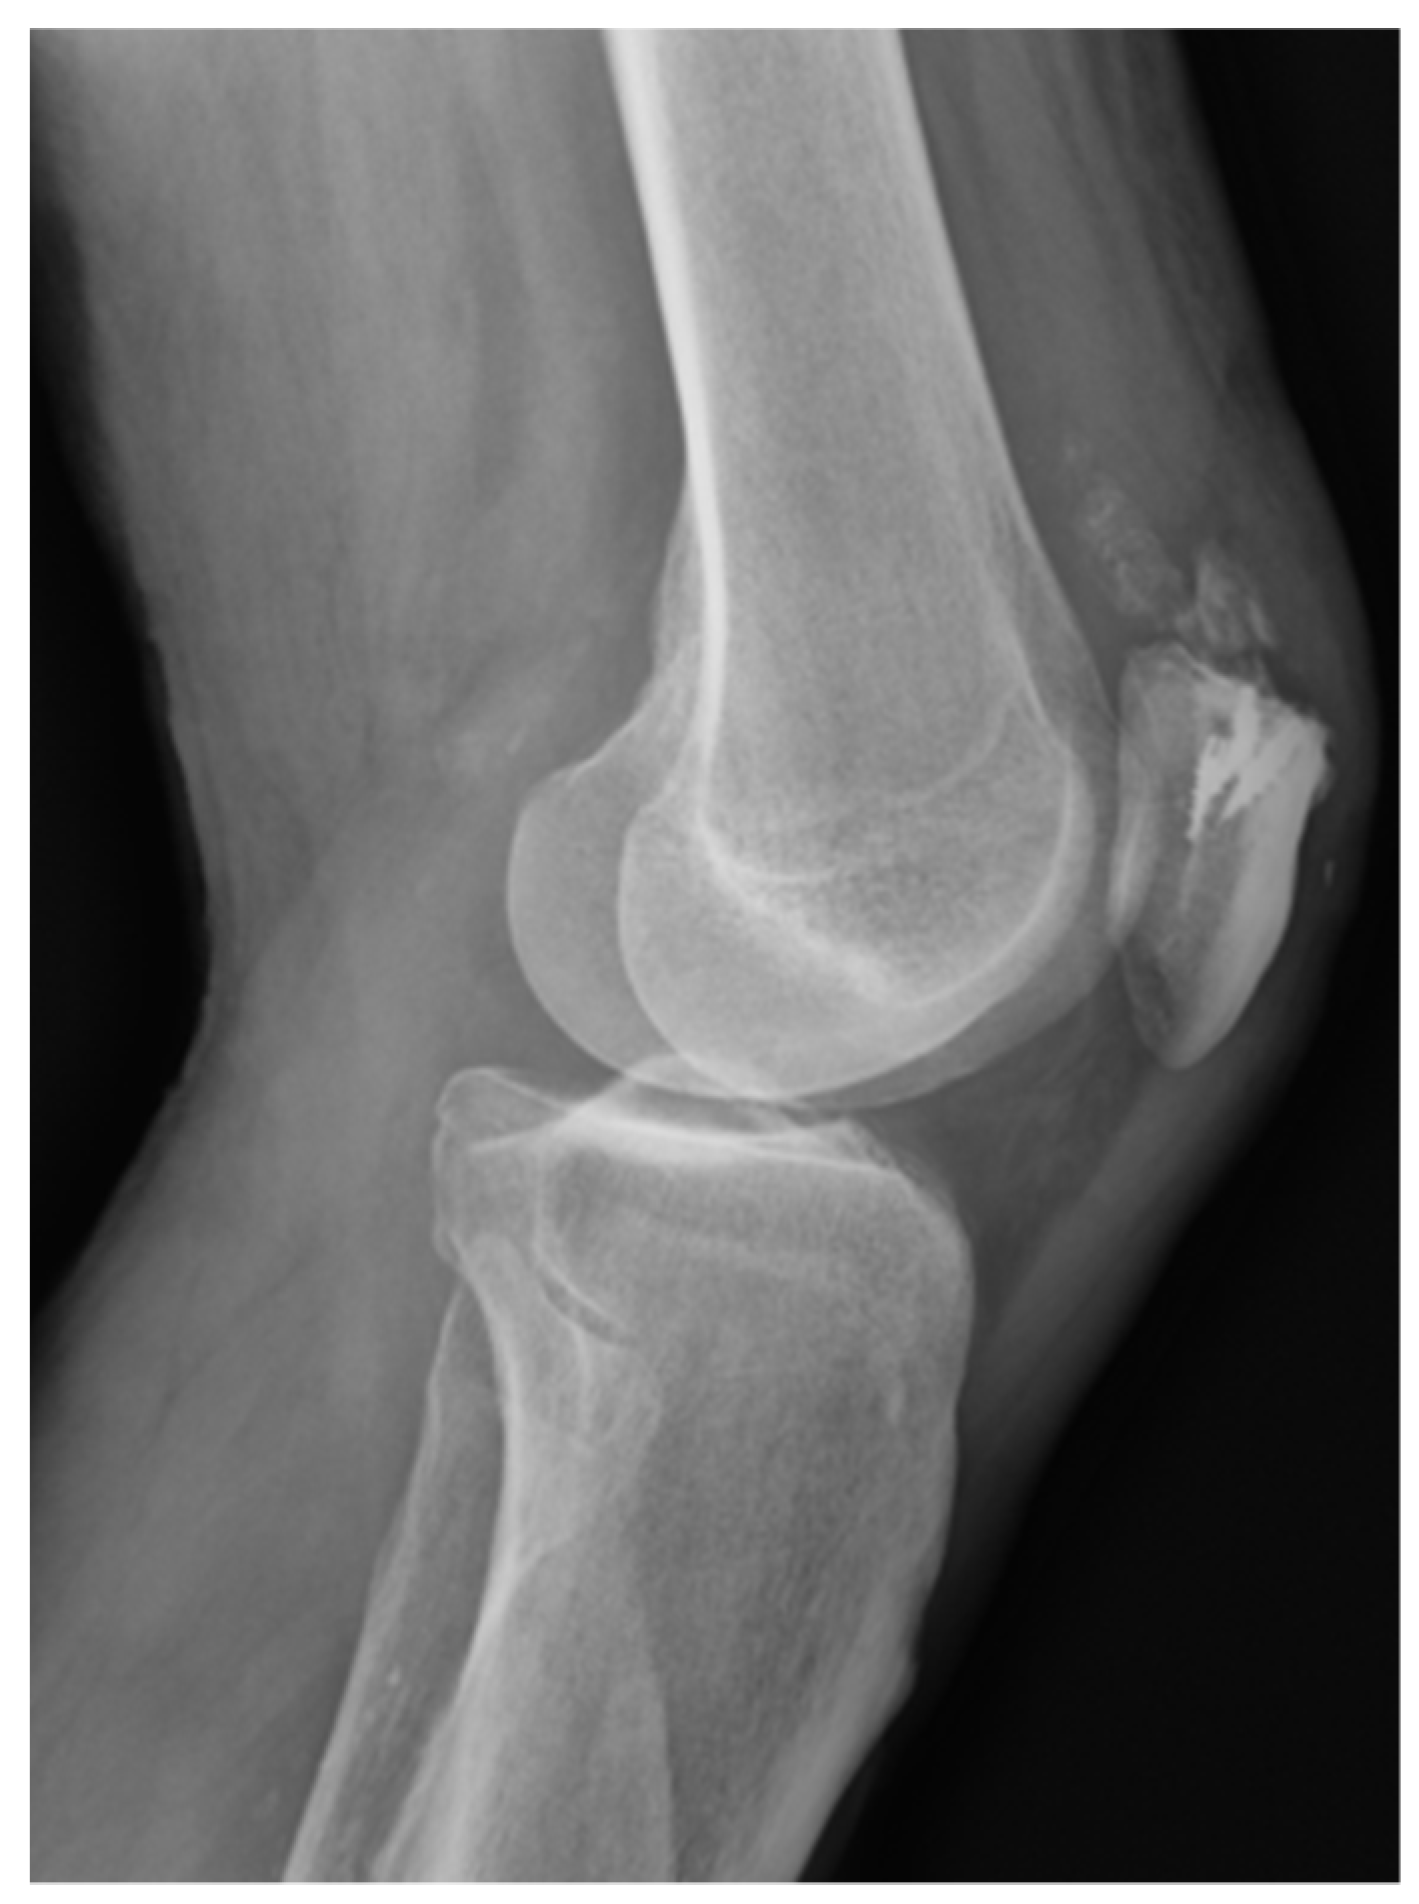

This technique also has the advantage that it can be used in pediatric patients, with the anchor implant placement achieved by radiographic control with a minimal incision and placing the anchor in the correct epiphyseal location to avoid injury of the cartilage growth zone and preserve the integrity of the bone growth plate (Figure 5). All patients returned to their usual work and sports activities without incidence of device-related or serious adverse events. In all cases, recovery of joint stability was achieved and complete recovery of full range of motion, except for the patient who underwent the manipulation under anesthesia who had a persistent 10° degree extension deficiency.

Figure 5. ACL reconstruction on physis open patients. Under fluoroscopic control on the operating, selection of the footprint and intruction the TWINFIX for LET reconstruction.